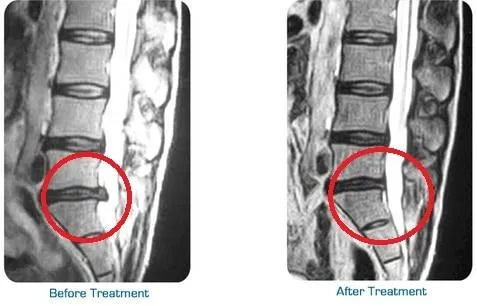

Healthy spinal discs require consistent blood flow to deliver oxygen and nutrients necessary for repair and maintenance. Unfortunately, when discs are compressed, this circulation can be restricted, slowing the healing process. Spinal decompression therapy works to improve blood flow by gently stretching the spine and reducing tension around the discs.

As circulation improves, your body can more effectively deliver essential nutrients to the damaged areas, accelerating the healing process. This enhanced nutrient exchange helps reduce inflammation and promotes tissue regeneration, supporting your spine’s natural ability to repair itself. By restoring proper blood flow, spinal decompression ensures long-term improvements in your spinal health.

Spinal decompression gently relieves pressure on the spine, discs, and nerves—helping reduce pain while improving movement and flexibility. When paired with laser therapy, which uses focused light energy to decrease inflammation and stimulate tissue repair, the healing process is accelerated.

Together, these therapies work synergistically to treat both the symptoms and root causes of pain, improve function, and speed recovery—without drugs or surgery. This comprehensive, non-invasive approach is especially effective for conditions such as herniated discs, chronic back pain, and soft-tissue injuries.